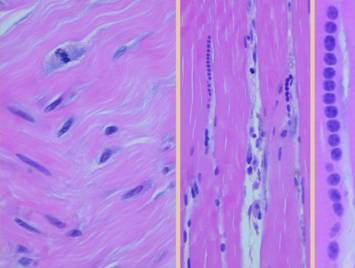

Left upper, the forearm contracture shown in a previous panel.  Integra was used to reconstruct skin after first excising the contracted scar.  Late results show no scar, no scar hypertrophy, no contractures.  Left lower, a keloid excised from behind the ear, skin then reconstructed preemptively with Integra to prevent recurrent keloid.  Late photo shows the area healed with no signs of scar hypertrophy.  Right, a pane of comparative histology.  Top row shows normal dermis, one view having been cut parallel to skin tension lines, the other orthogonal.  Whether seen on side or on end, normal dermis with normal elasticity and has an architecture of collagen bundles separated or porated with interstitial spaces which give it some deformability and pliability, typically greater in one direction than the other.  Middle row shows young scar and young Integra.  The scar is dense in collagen, no spaces, no opportunities for shifting and rolling of bundles, all oriented into locally thick bands but without an overall uniform direction, making the scar anisotropically stiff.  In comparison, young Integra has local fibrous foci which are separated from each other by the matrix, thereby maintaining interstitial porosity and the ability of domains to shift or distend relative to each other, a configuration and mechanics much more like normal dermis.  Bottom row shows scar and Integra in phases of late maturation after many years.  Both have remodeled away from their original appearance back toward normal dermis or fascia,  The difference is that young scar quickly becomes packed with immobile excessively dense collagen, and then it takes years to remodel back to normal stromal density, architecture, and mechanics.  Integra-CGM also takes years to remodel back to a strictly normal appearance, but it has the fundamental architectural and mechanical features of normal dermis right from the very beginning.

Left, a microscope image of normal wound healing.  The structure shown here is the prototypical wound.  Details of the structure and process will be explained in following panels.  Right, the microscopic appearance of fully regenerated Integra-CG matrix, the details likewise to be explained in following panels.  Even without explaining or focusing on specific details, the dissimilarity of the two can be appreciated.  Angiocytes and fibroblasts, vessels and connectives – that is all there is to these two tissues.  However, by supplying different “rules” or “subroutines” for the interaction and assembly of these elements, two different biomaterials emerge.  The rules or routines are based on the circumstances, reaction-to-injury versus embryonic regeneration.  The results have very different physical properties and implications for daily life, functional adaptations, and potential need for ongoing medical care.